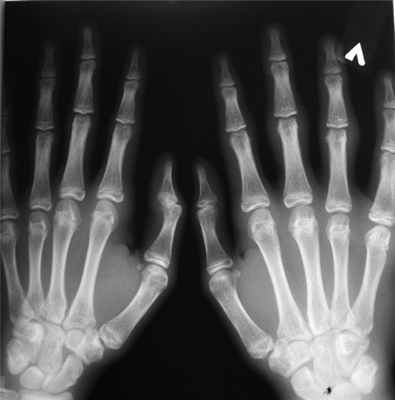

Рентгенограмма кистей (рис. 1): утолщение мягких тканей в области проксимальных межфаланговых суставов (изменения собственно суставов отсутствуют).

Рис. 1. Рентгенограмма кистей пациента Н.